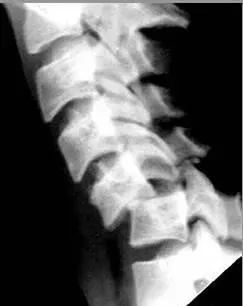

六、泪滴样骨折

屈曲压缩型骨折,可见泪滴样骨碎片向椎体前方分离移位,椎体变扁并向后方移位,椎小关节间隙及棘突间隙增宽,椎间隙变窄,70%合并神经损伤。